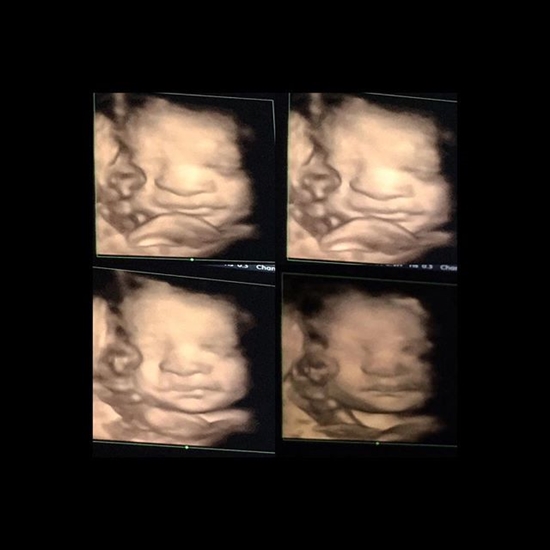

สุดตื่นเต้น ซี ฉัตรปวีณ์ อวดภาพอัลตราซาวด์ลูกน้อยครั้งแรก สุดขำแคปชั่นลูกอมนิ้วหัวแม่เท้าของตัวเอง พร้อมตั้งชื่อไว้ว่า น้องต้นไม้

จูงมือกันเข้าประตูวิวาห์ไปตั้งแต่ตอนปีที่ผ่านมา สำหรับเจ้าหญิงแห่งวงการไอที ซี ฉัตรปวีณ์ กับสามีหนุ่ม ก้อง อดิศักดิ์ ที่ล่าสุด (19 พฤศจิกายน 2558) สาวซีก็ได้แจ้งว่า ตอนนี้เธอได้ตั้งครรภ์เป็นที่เรียบร้อยแล้ว และเจ้าตัวก็ออกการการตื่นเต้นสุดขีด ด้วยโพสต์ภาพอัลตราซาวด์ลูกน้อยที่ได้ตั้งชื่อว่า น้องต้นไม้ เป็นครั้งแรกกันแบบซูมชัด ๆ ลงในอินสตาแกรมให้แฟน ๆ ได้ชมกัน

งานนี้ต้องบอกเลยว่า สาวซีดีใจกับการที่จได้เป็นคุณแม่มือใหม่ไม่น้อย เพราะนี่เป็นครั้งแรกที่ได้เห็นหน้าลูกขณะที่อยู่ในครรภ์ แต่ลูกน้อยเองก็น่ารักด้วยการอมหัวแม่เท้าของตัวเอง ทำเอาสาวซีติดแคปชั่นว่า "เห็นหน้าแล้ววว น้อง #ต้นไม้ เอานิ้วโป้งเท้ามาอม...เลิฟเลิฟ" ฮ่า ๆ น่ารักมั้ยล่ะ...